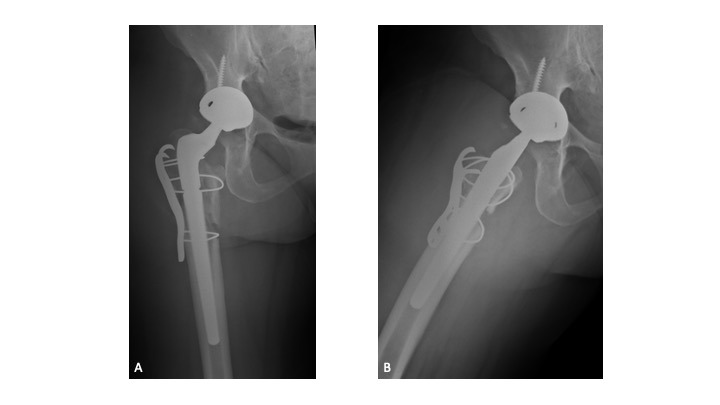

One month following brace removal (1/24/2020), the patient sustained another hip dislocation treated with closed reduction and subsequent revision arthroplasty (2/12/20) after ruling out PJI (ESR, 2 mm/h; CRP, 2.0 mg/L). Intra-operatively, an intra-prosthetic dislocation of the dual mobility construct was noted. (Figures 7a-d) The acetabular shell and femoral component were re-assessed and determined to be in appropriate position. The cemented dual mobility liner was exchanged for a 50mm cementable constrained liner (Freedom Constrained Liner – Zimmer Biomet, Warsaw, IN), and a 36-mm (+9-mm) constrained femoral head was selected to augment stability. (Figures 8a-b) Relevant radiographic measurements following primary and revision THAs is summarized in Table 1.